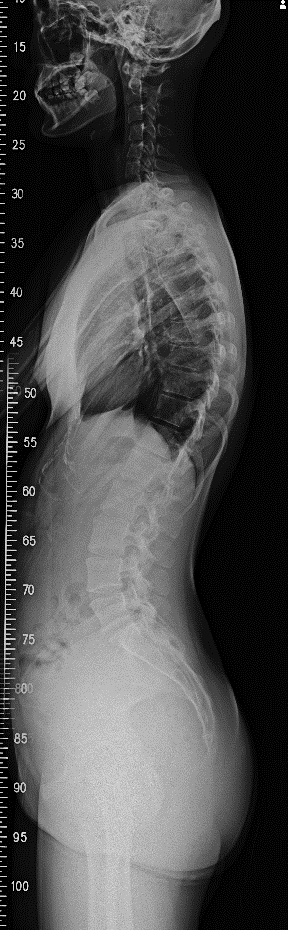

3. X光檢查如果以上檢查顯示出身體的不對稱,建議拍攝X光最能準確找出脊椎側彎

請注意一定要站立姿勢下拍攝,正面及側面各拍一張,以方便物理治療師做評估。